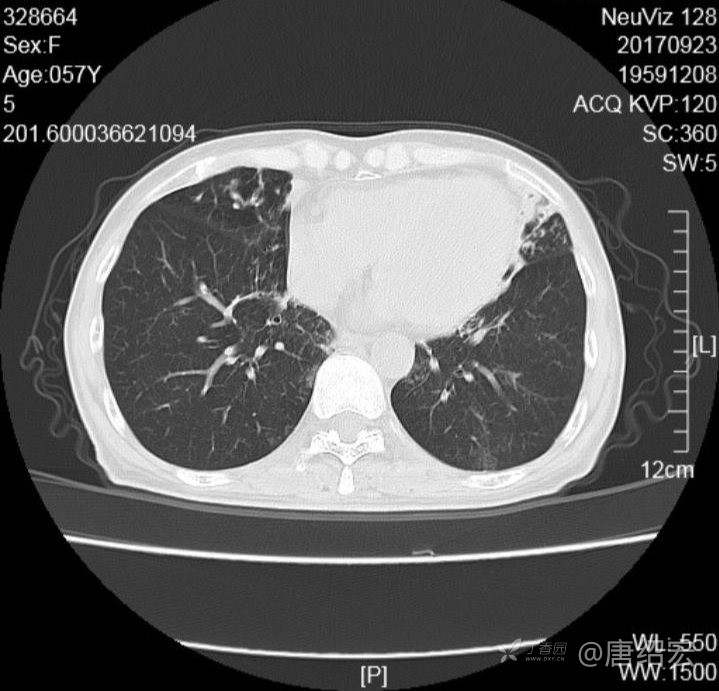

中年女性满肺树芽征还有支气管扩张,考虑什么疾病?

女,57岁,

主诉:发热、咳嗽、咯黄痰,胸闷3天入院。